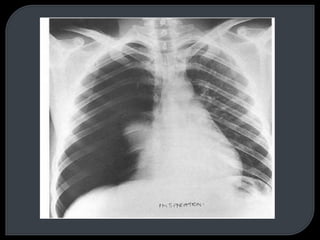

This document discusses x-rays and radiographic views. It begins with the discovery of x-rays by Wilhelm Conrad Roentgen. It then covers basic concepts like radiopacity and radiolucency. Several standard radiographic views are described like AP, PA, lateral, and decubitus. The document outlines how to analyze a chest x-ray using the ABCD method and lists common abnormal radiological signs. Radiographic technique factors like centering and inspiration level are also addressed.